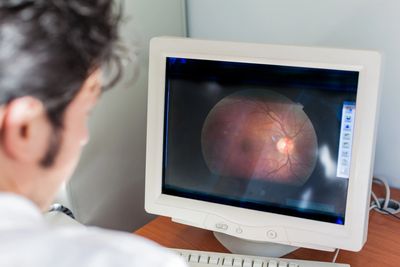

If you are living with diabetes, it’s important to have your eyes screened annually for diabetic retinopathy — a common diabetes-related complication that can lead to vision loss if left untreated. Early detection through routine annual screening is key to protecting your vision and overall health.

We are proud to offer monthly diabetic retinopathy screening clinics at our Indigenous primary care centre. If you have diabetes and have not had an eye screening in the past year, we encourage you to call and book an appointment.